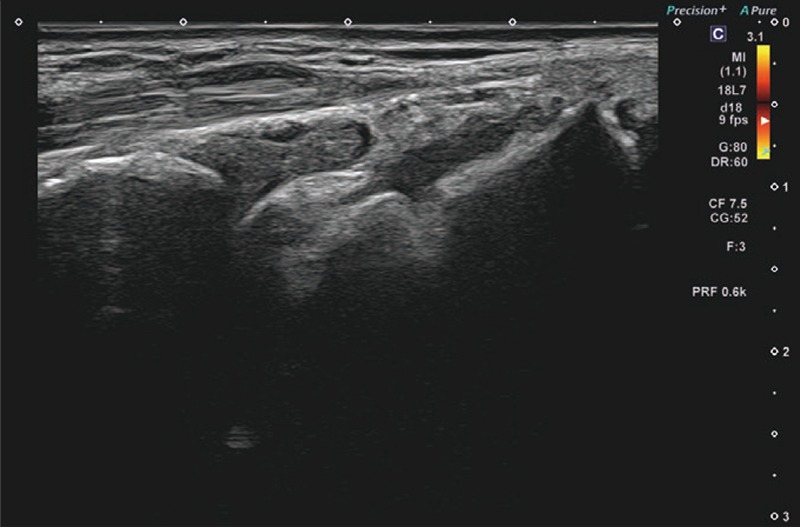

提示した症例画像はAplio meで撮影したRA患者さん手首のBモード画像、SMI画像、パワードプラ画像である。Bモードでは、ご覧の通り滑膜肥厚の低エコー域がクリアに区別できている(画像1)。Superb Micro-vascular Imaging(SMI)の血流は増殖した滑膜の部分に一致しており、血管からのはみ出しもなく血流を正確に検出している(画像2)。パワードプラでは、SMIと比較してブルーミングは存在するものの、モーションアーチファクトがなく、少々あったとしても素早く消失するので、走査時のストレスがなかった(画像3)。もちろんグレード1の血流も正確に検出できる。

RA症例画像

(部位:手首、超音波検査装置:Aplio me)

画像1 Bモード 画像1 Bモード